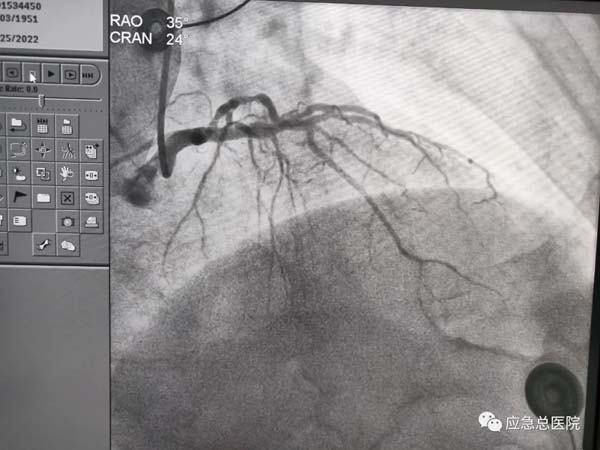

手术前

生命在接力。来到应急总医院后,为患者第一时间进行造影检查,结果提示:三支病变,前降支近端100%闭塞,也就是说供应心脏的三条血管均有严重的狭窄,而最主要的血管——前降支已经完全堵死,晚一点救治后果不堪设想。吴迪教授第一时间研判:务必马上开通闭塞血管,一刻都不能耽搁!因为应急总医院有一支经验丰富的介入团队,在吴迪教授的指导下,在范煜东副主任的熟练操作下,在张子龙副主任医师、张庆军主治医师及导管室护士、技师的通力配合下,病人的闭塞血管及时开通,如久旱甘霖般将鲜活的血液重新给濒临坏死的心肌细胞。手术一做完,病人就长舒一口气:“不疼了!舒服了!”在手术室门口焦急守候的家属,此刻喜极而泣。看看时间,从张大爷到光熙医院就诊,再转运到应急医院完成手术,仅用了50分钟。